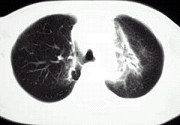

- 单项选择题淋巴瘤患者放疗后3个月出现气急咳嗽,CT如图, 应考虑为 ( )

A、陈旧性结核

B、放射性肺炎

C、浸润型肺结核

D、瘢痕癌

E、硅沉着病结节